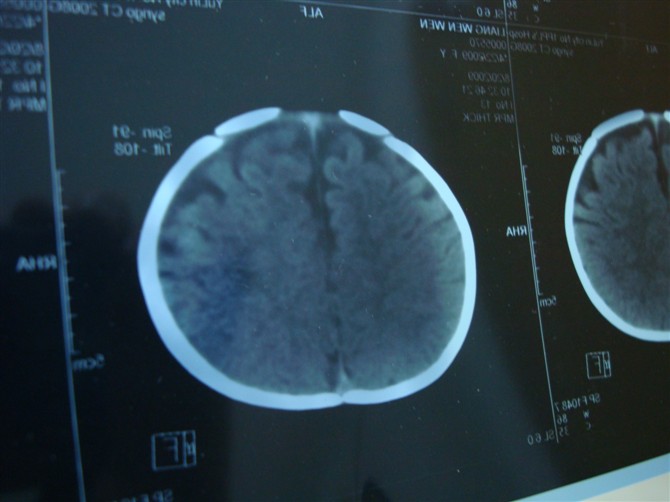

外部性脑积水,在第四军医大出版的《小儿ct诊断图谱中》诊断标准。书中列举四条标准:1。额顶部颅壁下间隙增宽在6-10mm;2。前纵裂增宽;3。脑室可增大或表现正常;4。属自限性疾病,1岁半以后可表现正常。 现在叫脑外间隙增宽 外部性脑积水国外文献又称其为 “假性脑积水”。临床可分为特发性外部性脑积水和继发性外部性脑积水。

1.特发性外部性脑积水 表现为不明原因的抽搐或(和)头围异常增大,ct改变符合外部性脑积水特征。特发性外部性脑积水原因还尚不清楚,可能与蛛网膜颗粒的发育滞后、发育不全或功能低下有关。

2.继发性外部性脑积水 继发于脑缺氧、硬膜下血肿、脑室出血、蛛网膜下腔出血、脑膜炎以及颅脑外伤后具备上述特征者。

特发性外部性脑积水的发病机理目前亦不十分清楚,但多数学者认为与蛛网膜颗粒发育迟缓,吸收脑脊液的功能发生障碍有关。继发性外部性脑积水主要是因脑膜炎、脑室出血、蛛网膜下腔出血等,使蛛网膜发生粘连、肥厚、增生,形成蛛网膜机械性梗阻或炎症性改变而影响脑脊液的吸收。